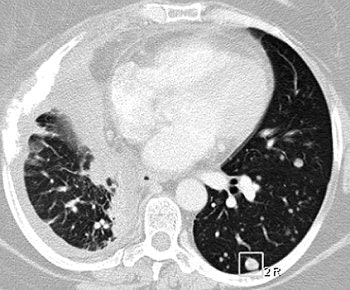

| A 47-year-old woman with numerous metastatic nodules from small cell lung cancer in right lung and unmatched nodule in superior segment of left lower lobe. Above, transverse CT image shows baseline findings. Below, transverse reformatted CT image shows follow-up findings. Overall matching rate was 0 (0/10). Infiltration of lung cancer was markedly increased, with complete collapse of upper lobe of right lung during interval. |